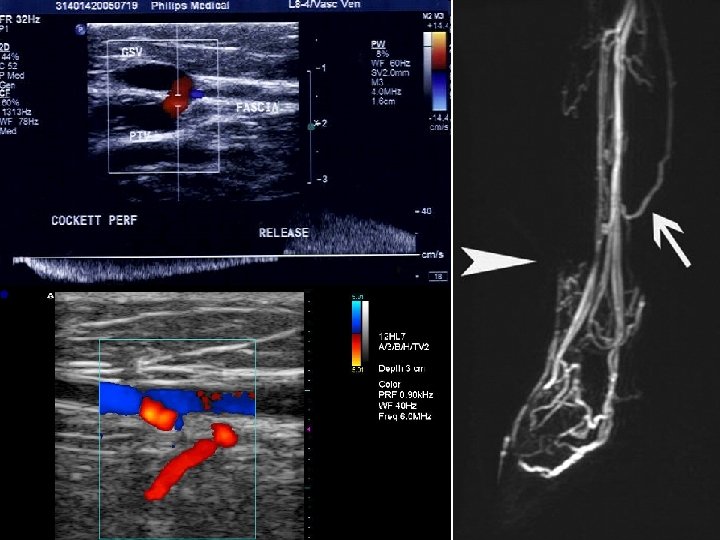

Venae perforantes • simple, double or multiple • run with small artery and cutaneous nerve (Staubesand‘s triad) • 6 groups: foot, ankle, leg, knee, thigh, buttocks • eponyms: Cockett, Boyd, Dodd • e. g. : venae perforantes cruris posteriores tibiales = Cockett‘s perforators – interconnect v. s. m. accessoria posterior and venae tibiales posteriores – 18. 5, 13. 5 a 7 cm proximal to sole 4 -mm tibial perforator

Vein of LL – 3 D-flebo. CT VSP varices Dodd